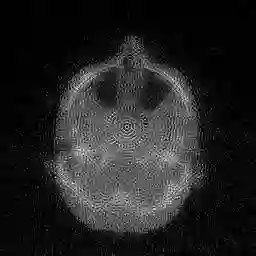

In this work, we propose Regularization-by-Equivariance (REV), a novel structure-adaptive regularization scheme for solving imaging inverse problems under incomplete measurements. Our regularization scheme utilizes the equivariant structure in the physics of the measurements -- which is prevalent in many inverse problems such as tomographic image reconstruction -- to mitigate the ill-poseness of the inverse problem. Our proposed scheme can be applied in a plug-and-play manner alongside with any classic first-order optimization algorithm such as the accelerated gradient descent/FISTA for simplicity and fast convergence. Our numerical experiments in sparse-view X-ray CT image reconstruction tasks demonstrate the effectiveness of our approach.